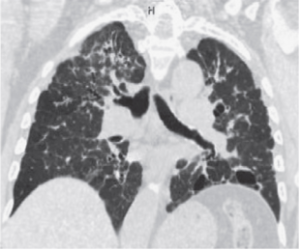

Под этим термином подразумевается изменение нормального расположения видимых структур легких: в первую очередь легочных сосудов, бронхов и листков междолевой плевры. Нарушение легочной архитектоники определяется в виде необычного (патологического) расположения бронхов, сосудов, щелей или перегородок в результате их перемещения в легочной ткани. Эти изменения обычно вызваны диффузным или локальным поражением паренхимы легких (см.), например при хронических инфекциях, интерстициальных заболеваниях, аномалиях и пороках развития и т.д.

Измененный участок уменьшается (фиброз, ателектаз - см.) или увеличивается (вздутие) в объеме, что приводит к перераспределению элементов легочного рисунка на рентгеновских снимках или к нарушению нормального хода сосудов и бронхов при КТ.